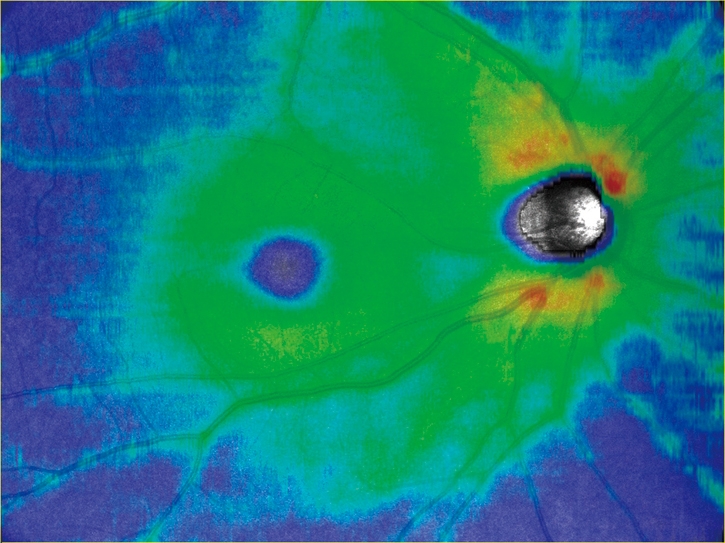

任意設定により5種類(初期設定:網膜全層、表層、深層、外層、脈絡膜)のパノラマが同時に自動合成できます。

網膜全層 HD4 4.5×4.5mm 6枚 パノラマ |

網膜表層 |

網膜深層 |

網膜外層 |

脈絡膜 |